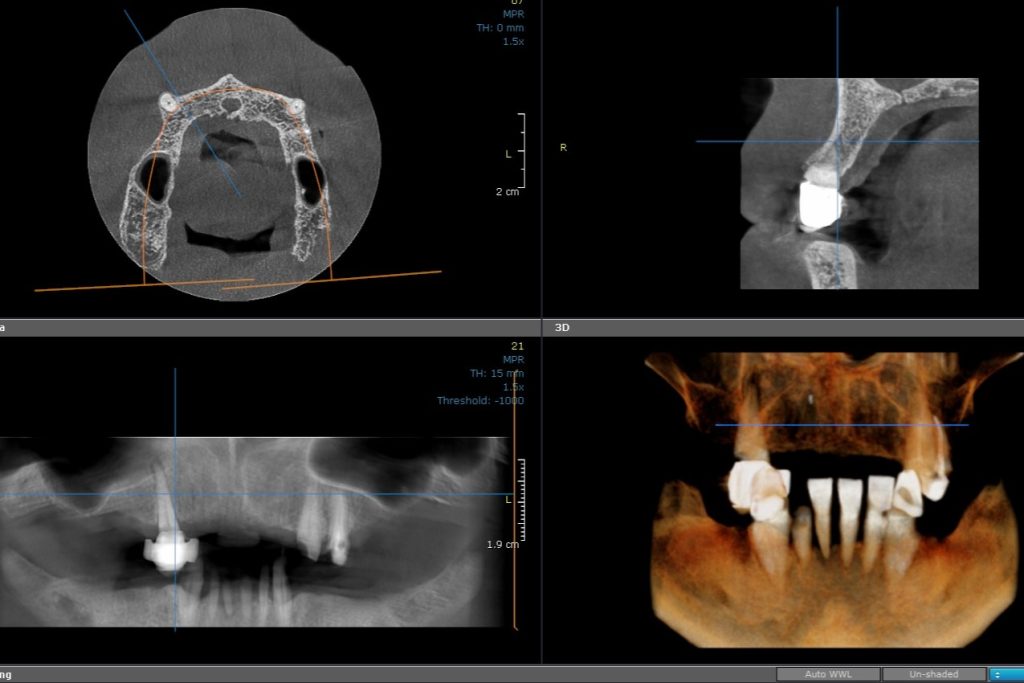

CBCT Mandibula

CBCT analysis of both jaws show available bone for fixed implant born dental restoration